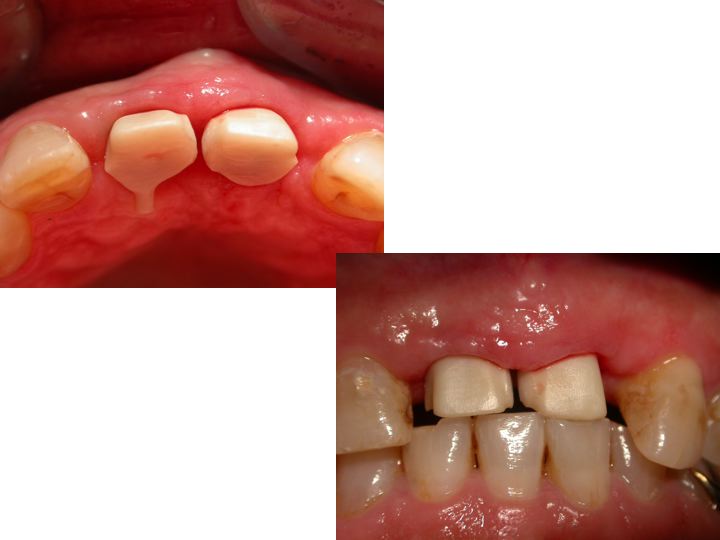

Split-crest technique associated to immediate implant positioning and temporising. Use of oral electro-welding to stabilize implants during healing time. A case report. Avvanzo P. Abstract Implant rehabilitation of the edentulous maxilla may be somewhat problematic because of anatomic situations involving insufficient bone thickness or mandibular teeth position. One approach in this situation is localized horizontal ridge augmentation with the split crest technique. This surgical approach allows the external cortical plate of the maxilla to be moved in a buccal direction to gain an increase in width to introduce implants of appropriate diameter and with an appropriate angle in spite of lower arch. We tried to associate split crest technique to immediate implant positioning and temporising using an oral electrowelder to stabilize implants during healing time. Introduction Bone resorption in anterior maxillar edentulous areas can be so important to affect implant diameter and position choice, which may not be ideal for the teeth to be replaced. The result can be a failing position and a smaller diameter than necessary. Another failing result is an insufficient esthetic aspect of the tooth-gingiva architecture being resorbed the washboard form of the flattened alveolar bone. If bone graft techniques are not considered, the first option treatment is the thikness augmentation separating the cortical plates and creating a space which can be filled with bone , bone substitutes or left opened using implants as space keeping devices. In all cases no load has to be applied(R) on the area. The Split crest technique is undoubtly an advantageous procedure to obtain a correct alveolar bone thickness in resorbed edentulous ridges avoiding in the same time bone grafts from donor sites reducing morbility for a second surgical area and diminishing the size of incisions in the first one. It takes advantage of the growth potential of bone when undergoes to osteogenetic distraction and it has the same healing pattern of extraction sites. Since the space between the two cortical plates is still not mature bone the standard protocol is to permit healing and maturing before implant placement. There are a lot of modifications to this technique regarding bone substitutes or direct implant positioning avoiding the direct load on the area. The technique explained in this case report schedules the use of conic, large screw, single stage implants, placed after the crest splitting and immediately temporised. In multiple implants positioning, to avoid micro-movements on immediate loaded implants a titanium bar has been electro-welded to the abutments temporarily, thus creating a solidarised system even stronger than single implants. Even if in this case report the cortical plates were thick and solid, the chance for micro movements was real, since implant restorations involved the upper central incisors and their ability to engrave food. Since it is quite difficult divert food incision to other teeth when such central teeth are involved in restoration, it was decided to use electro-spot-welding to solidarise implants.